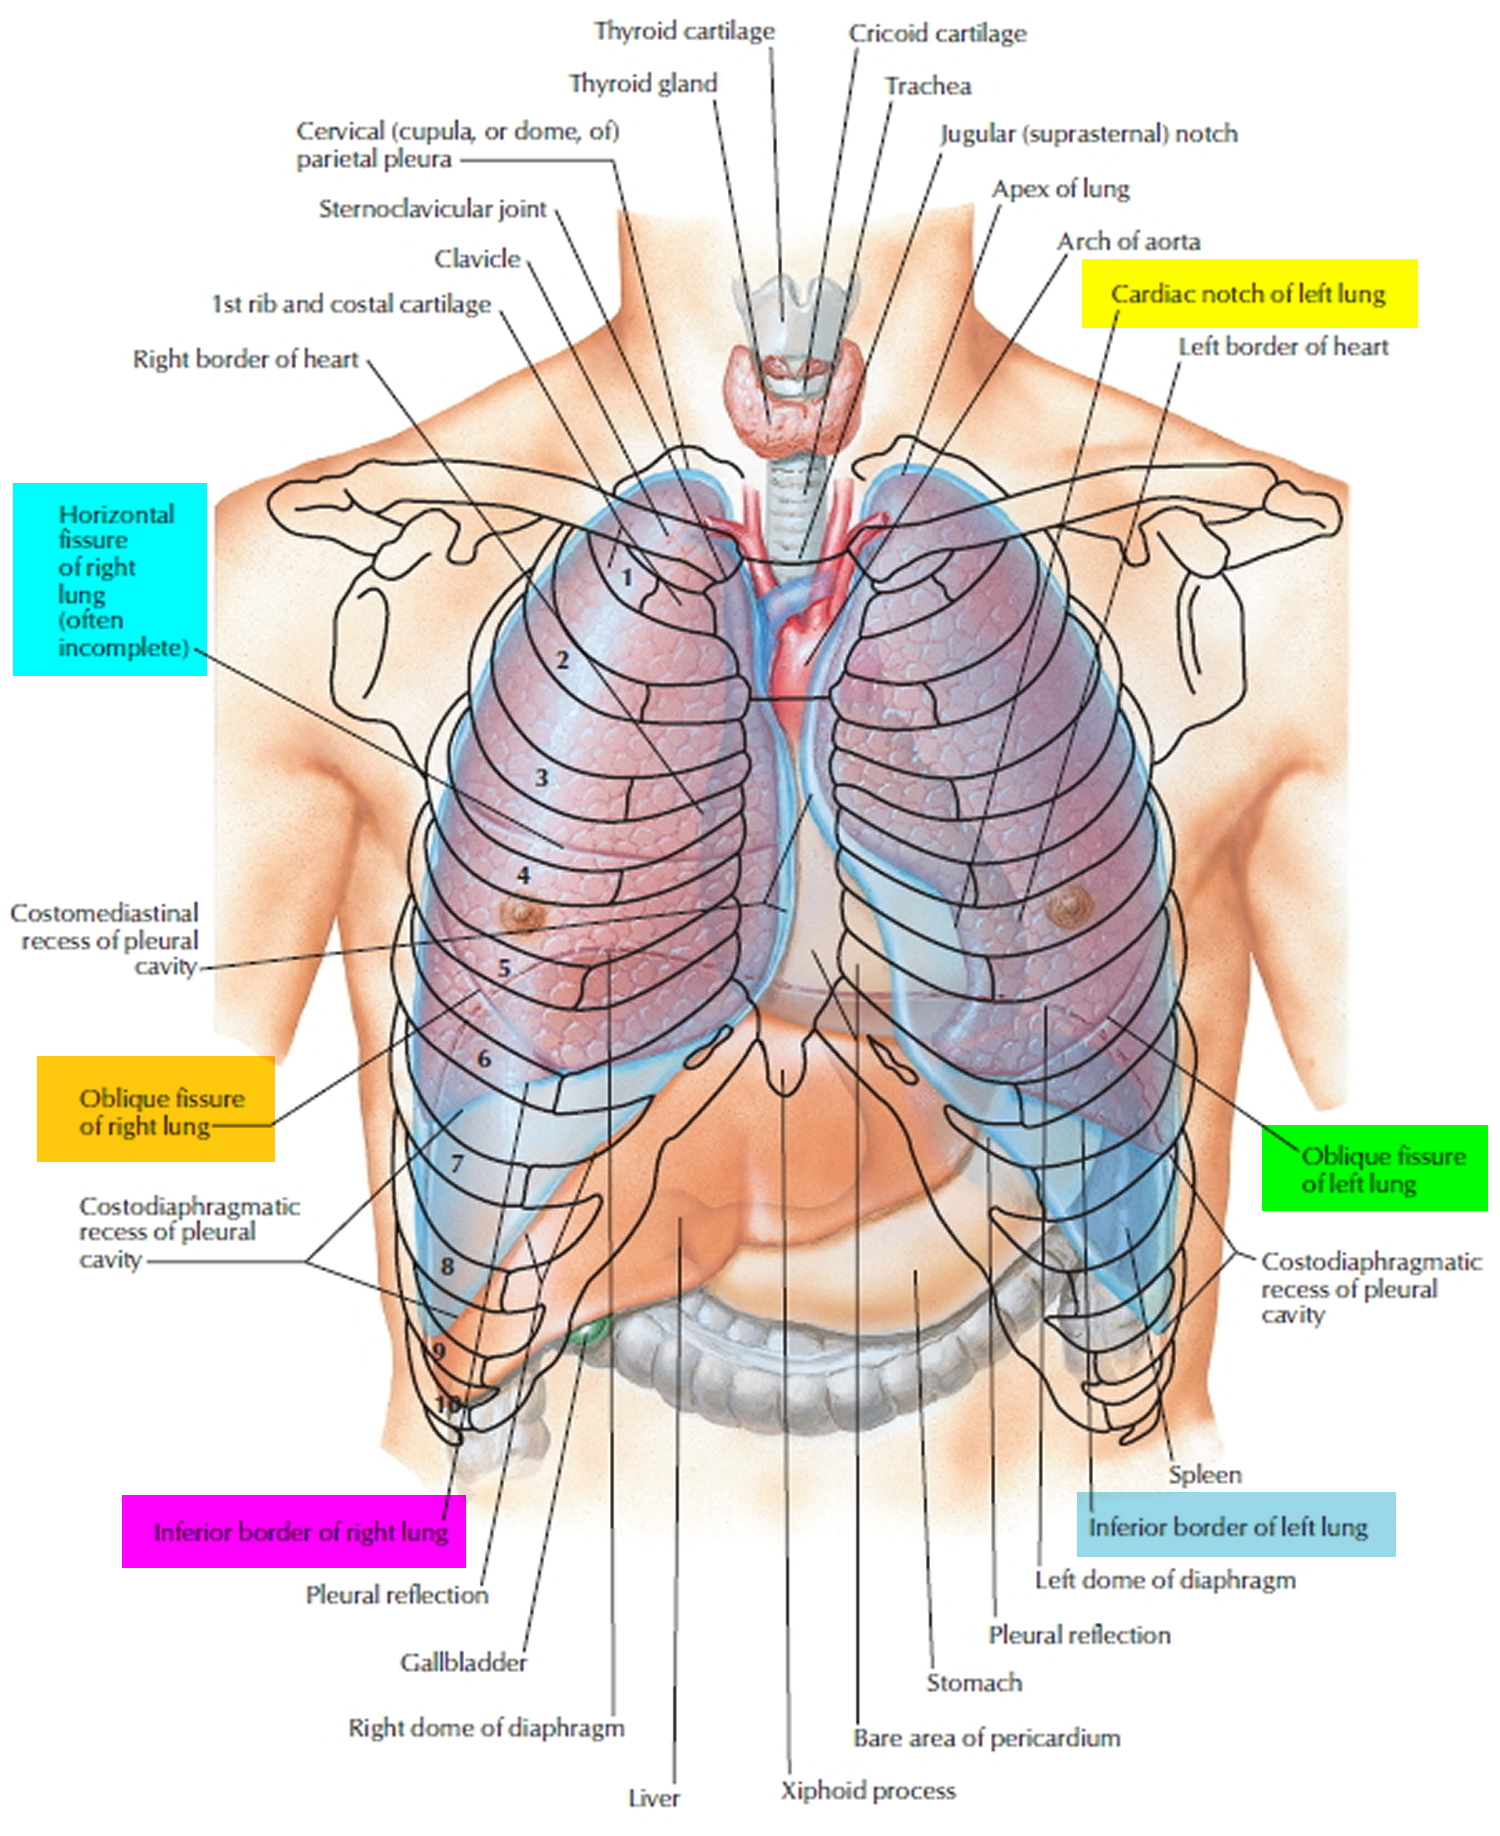

Анатомия Сердца: Расположение и Функции